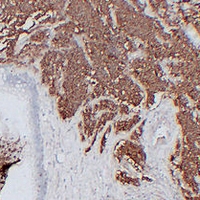

Immunohistochemical analysis of CD56 staining in human small cell lung carcinoma formalin fixed paraffin embedded tissue section. The section was pre-treated using heat mediated antigen retrieval with sodium citrate buffer (pH 6.0). The section was then incubated with the antibody at room temperature and detected using an HRP conjugated compact polymer system. DAB was used as the chromogen. The section was then counterstained with haematoxylin and mounted with DPX.